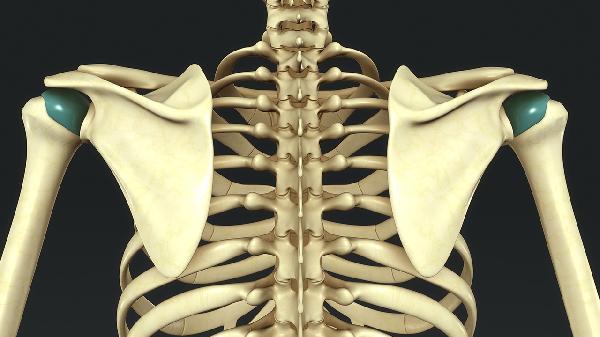

胸椎痛可能由肌肉劳损、骨质疏松、胸椎间盘突出、胸椎关节紊乱、强直性脊柱炎等原因引起。胸椎痛通常表现为局部疼痛、活动受限、放射痛等症状,可通过物理治疗、药物治疗、手术治疗等方式缓解。

胸椎痛可能与关节错位、韧带松弛等因素有关,通常表现为活动时弹响、晨僵等症状。患者可通过手法复位、牵引等方式治疗,日常需避免突然扭转身体。